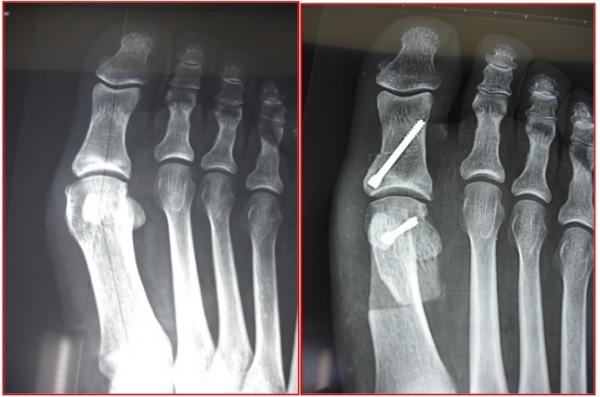

HALLUX VALGUS

Il s’agit d’une déformation qui crée une saillie osseuse sur la partie médiale de l’hallux, à l’origine de phénomènes douloureux et d’une gêne au chaussage. Il s’agit de la déformation la plus fréquente de l’hallux. Elle touche préférentiellement les femmes, parfois dès le plus jeune âge. On ne connaît pas réellement les causes de cette déformation mais l’origine congénitale semble la plus vraisemblable

Chirurgical :

Les techniques « conventionnelles (ciel ouvert) » permettant, sous contrôle de la vue de corriger la déformation.

Au contraire, les techniques « percutanées » utilisent plusieurs incisions millimétriques, permettant le passage d’instruments spécifiques qui sont guidés sous la peau par un contrôle radiographique.

Anesthésie locorégionale et chirurgie ambulatoire

Pansement post op soit à changer par une infirmière à domicile ou à conserver en fonction de la technique opératoire

Chaussure médicale avec semelle rigide est prescrite avec appui autorisé mais le moins possible